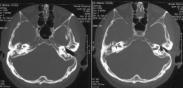

中耳癌為發(fā)生于中耳的少見惡性癌腫,多為原發(fā)。中耳癌的誘因,很可能是中耳的長期感染,據(jù)統(tǒng)計(jì),多數(shù)中耳癌患者有慢性化膿性中耳炎的病史。其發(fā)病年齡多為40~60歲,本病病理是以鱗狀上皮細(xì)胞癌最常見,基底細(xì)胞癌和腺癌在中耳很少見。